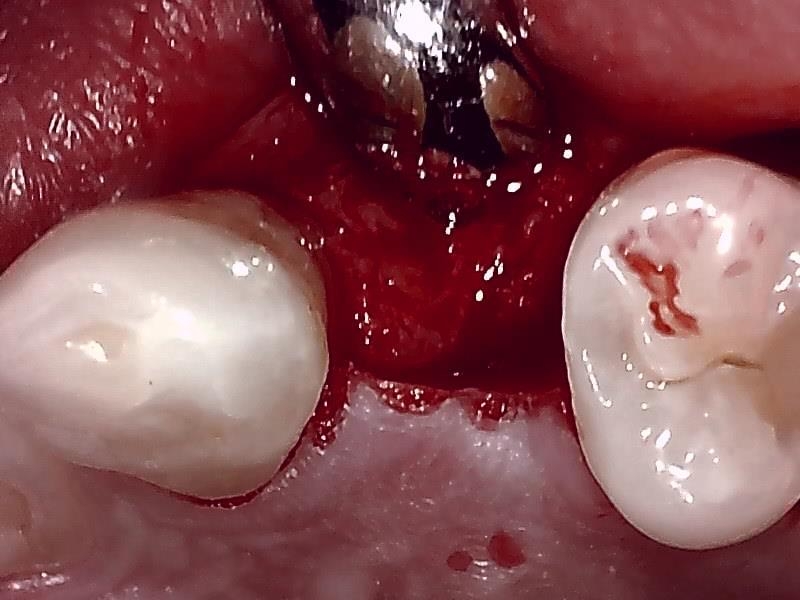

切開して歯肉剥離

術前の顎堤

顎堤部 歯槽骨にドリリングする。